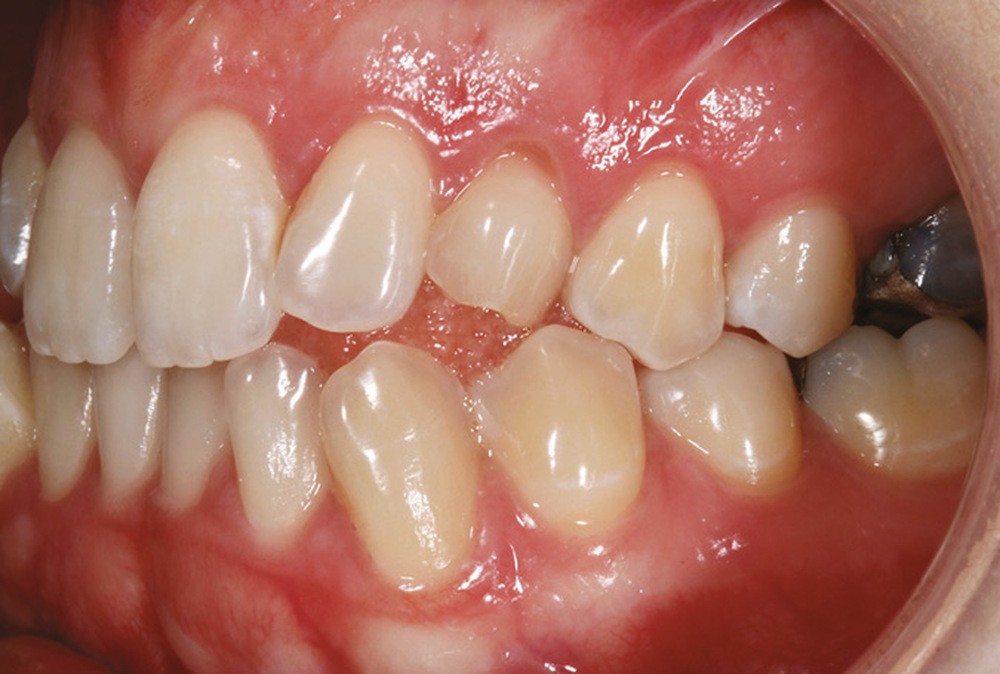

La patiente, âgée de 24 ans, en bonne santé générale, consulte en orthodontie pour raisons esthétiques. Elle présente une classe III squelettique par rétrognathie maxillaire sur un schéma facial hyperdivergent (fig. 1a-b).

Sur le plan dentaire, on note l’absence des canines maxillaires permanentes sur l’arcade et la persistance de 63. Il existe une DDD par défaut maxillaire (indice de Bolton antérieur 90,2 %) due à l’absence des canines sur l’arcade, mais aussi à une dysharmonie de forme des dents maxillaires (fig. 2a-e).

Sur le plan fonctionnel, la patiente présente une déglutition atypique associée à une posture linguale basse.